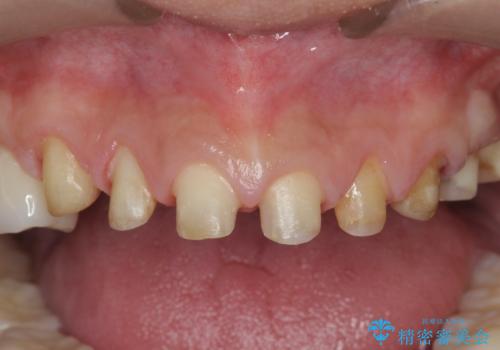

歯ぎしりですり減った 前歯の見た目を回復したい

- 歯ぎしり・嘔吐症により歯がすり減ってしまい、色調・見た目を改善したいと来院されました。

神経を温存したまま仮歯に置き換え、噛み合わせの安定を確認したのちに すり減りに強いジルコニアクラウンで最終的な仕上げを行います。